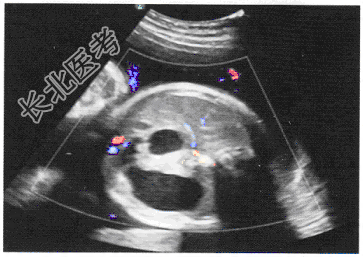

- 单项选择题患者,女, 30岁,孕28周, 胎儿超声检查如图,最可能的诊断是

A、肾积水

B、淋巴管囊肿

C、十二指肠闭锁

D、食管闭锁

E、肛门闭锁